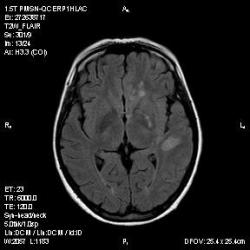

Из анамнеза - Женщина 45 лет. За год похудела на 15 кг (со слов матери), в последние месяцы случались эпизоды потери сознания. Онкозаболеваний и прочая в анамнезе нет. Сознание спутанное, из особенностей в анализах только подъем амилазы крови.

"Раскрою" карты. Мы подумали о синдроме MELAS (mitochondrial encephalomyopathy, lactic acidosis and stroke) - дословно, митохондриальная энцефаломиелопатия, лактоацидоз и инсульт. В качестве дифференциальной диагностики можно было бы предположить вирусный энцефалит, но опять-таки, расположение очагов смущает - только с одной стороны и в абсолютно различных структурах.

В данном случае мы видим импульную последовательность FLAIR - режим с подавлением сигнала от воды, поэтому ликвор гипоинтенсивен, а также (вторая серия) - изображения, взвешенные по T1 после введения контрастного препарата. На T1 жидкость (ликвор) также представляется гипоинтенсивной. Зато на этих сериях гиперинтенсивны сосуды, т.к. контрастное вещество циркулирует в кровяном русле.

Изменения носят сосудистый характер. Процесс достаточно острый, имеется объемное воздействие, борозды левой гемисферы компремированы. По поводу MELAS синдрома очень сомневаюсь, почему поражена только левая гемисфера? Надо делать МР-ангиографию, смотреть нет ли стеноза

MELAS синдром - дебютирует с детских лет, характерен целый комплекс неврологических проявлений, заболевание генетическое, поражение системное, хотя есть множество вариантов митохондриального поражения, все же сомнительно. Хотелось бы акцентировать внимание, что гиперинтенсивные очаги есть в мозолистом теле, поражены выражено перивентрикулярные отделы, U -пути, белое вещество, поэтому так категорично демиелинизацию не вычеркивала бы из дифряда ( хотя тоже нетипично односторонее поражение). Думаю, для объективных выводов все же мало общей информации о пациентке, были ли клинические эпизоды раньше, чем объяснить такую потерю веса (возможно есть проявление паранеопластического синдрома?). Ну и МРТ-контроль в динамике, ангиография.

Да, неоднозначный случай. Точно не РС и не ОНМК. Я бы написала асимметричную лейкоэнцефалопатию неясного генеза. Можно было бы думать о лимфоме (полифокальное поражение, да еще мозолистое тело вроде бы задействовано (эх, сагиттальчики бы)). Но! Учитывая отсутствие накопления КВ.... Ну и надо исключать интоксикацию, всяческие аутоиммунные процессы (в т.ч. и васкулиты), сахарный диабет, ну и естественно наследственную патологию обменных процессов. УУУх! Вот.......

Имхо ишемический онмк в бассейне сма. Особенно показательны 5-й и 6-й файлы, отграничение как раз на границе бассейнов средней и перикаллёзной. Плюс одностороннее поражение.

Учитывая наличие повышенного уровня амилазы, похудание - вероятно проблемы с поджелудочной, в том числе и опухоль. Может быть нарушение коагуляции (гиперкоагуляция с образованием тромбов). Сильно я нафантазировал?

Не сильно, похоже онкопатология.